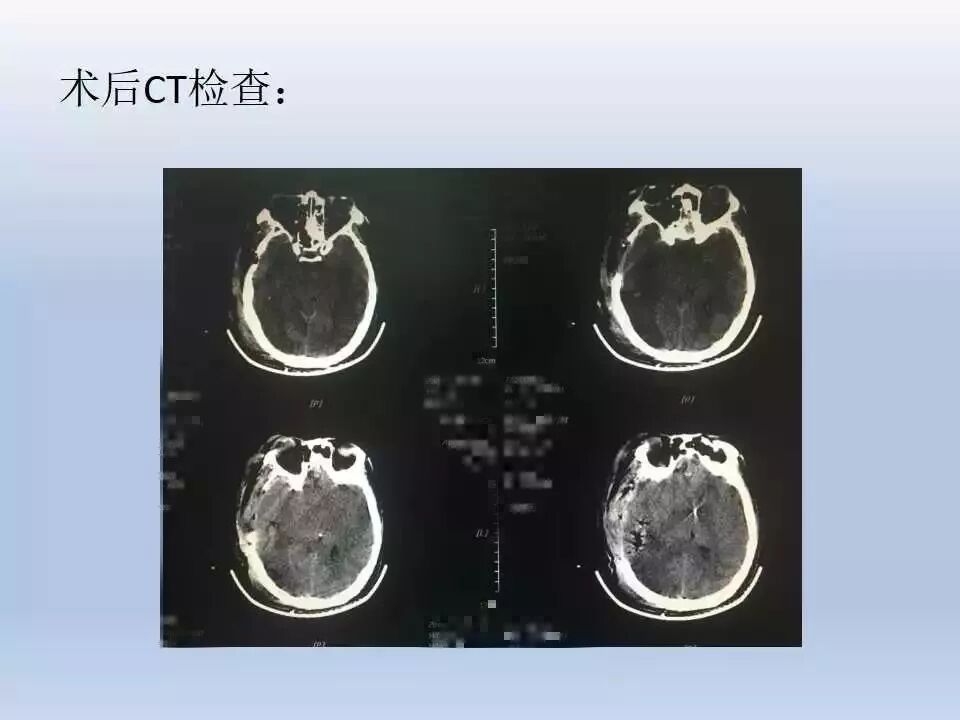

该患者经紧急抢救后,立即进行标准大骨瓣开颅减压、清除血肿,术后ICP监测、镇静镇痛、亚低温治疗、气管切开等一系列的规范化治疗措施。术后早期开展康复治疗。术后约2月早期进行颅骨修补,避免去骨瓣减压所带来的并发症。最终取得比较好的治疗效果。这充分说明规范化治疗有助于提高颅脑创伤的治疗效果。